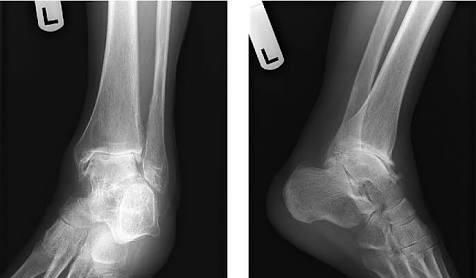

那么在外伤的过程当中,尤其是骨折的过程当中暴力一旦伤及到关节,很多人在x线上会明确的看到骨头的折断,但是在骨头上面尤其是涉及关节的骨头上面,软骨也会发生明显的撕裂。(下图就是典型的关节骨折软骨骨折的关节镜下所见)相信不用学医,也会看到骨折以后关节的软骨也会有明显的折断。

因为关节软骨是一种不可再生的结构,如果骨折对位比较好,软骨对位也比较好的话,骨折愈合以后,可能不会有太大的影响。但是毕竟裂痕已经形成了,将来就很有可能会诱发软骨的退变,导致创伤性关节炎的发生。而如果骨折对位的比较好,关节软骨没有对位的特别好,那么就有可能很快发生创伤性关节炎。